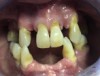

A 51-year-old man presented for a new patient dental appointment (Figure 8 through Figure 11). His health history revealed mild systemic disease. The patient was receiving simvastatin 20 mg and lisinopril 10 mg. He had a full-mouth set of x-rays and oral photographs taken at his initial appointment. At the next appointment, a debridement was performed. At the third appointment, pocket depths were measured and a diagnosis was made of moderate periodontal disease; a treatment plan was formulated, followed by four quadrants of SRP treatment. The patient was placed on a 3- to 4-month recall cleaning visit. At the fifth appointment, the patient's oral cavity was re-evaluated and doxycycline hyclate 10% was delivered subgingivally in the areas of tooth Nos. 5, 14, 15, 18, and 19. The patient was provided oral hygiene instructions and a home care plan. Several products and methods were introduced, including periodontal prescription trays with 1.7% of hydrogen peroxide placed in the trays and used twice daily for 20 minutes each time. The patient was also placed on stannous fluoride.